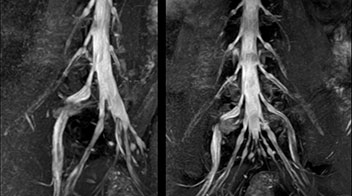

“In patients with lower extremity neurological symptoms, NerveVIEW helps us to determine the disease matching the patient’s symptoms by directly visualizing the nerves. We use the sequence mainly, when there is suspicion of intraforaminal stenosis, extraforaminal stenosis or lateral disc herniation, which is often based on routine T2- and T1-weighted images. Additionally, the excellent depiction of the course of nerves makes NerveVIEW a good navigator when applying treatment such as block therapy or surgery.”

“For example, in sagittal images, when the presence of fat is observed in the intervertebral foramen, it suggests that there is a margin around the nerve. Similarly, the absence of fat indicates that the nerve is being compressed. So, we used to deduce nerve compression indirectly. With NerveVIEW, however, we can observe the condition of the nerves directly, regardless of the presence or absence of fat. We always prefer such direct observation of anatomy over having to make an inference about it.”

“The intra-luminal signal of veins, especially around the intervertebral space, can be suppressed well with NerveVIEW. As a result, we can easily observe the detailed nerve structure around the posterior ganglion,” he says. “This is why we use 3D NerveVIEW for intraforaminal stenosis and extraforaminal stenosis/herniation (lateral disc herniation). On the other hand, if herniation is suspected to exist inside the dorsal root ganglion (DRG), balanced TFE or ProSet-FFE is applied. NerveVIEW is not suitable for evaluating the median type of herniation.” The SE-EPI DWI-based method for MR neurography works well for large FOV exams like whole-body MRI, but focal examination of nerves is often limited by the attainable spatial resolution (both inplane and slice direction) and geometric distortion. “3D NerveVIEW achieves higher in-plane resolution – close to our other routine spine sequences – and the source images can be used instead of adding a fat-suppressed T2-weighted sequence,” Tanji says.

According to Tanji, methods such as ProSet FFE, STIR or 3D VISTA are anatomically nonselective because background signals, for instance from blood vessels, often interfere with nerves, which hampers evaluation of details, especially at the peripheral side of the nerves.

“For both brachial and lumbar plexus, we are currently using a 230 mm FOV and voxels of about 1 x 1 x 2 mm acquired (1 x 1 x 1 mm reconstructed). This provides us a good representation of the nerves, even though this FOV is relatively small. Regarding the inplane resolution, we hope to be able to bring that down to 0.7 mm, similar to our typical 2D multislice T2W images,” says Tanji.